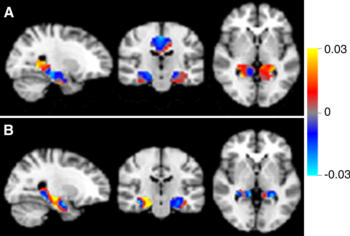

With automated methods, age- and sex-adjusted arterial spin labeling (ASL) perfusion maps can be used to classify and predict diagnosis of Alzheimer’s disease (AD), conversion of mild cognitive impairment (MCI) diagnosis to AD, stable MCI, and subjective cognitive decline (SCD) with good to excellent accuracy and area under the receiver-operating characteristics curve (AUC) values, according to a new study published in Radiology.

Lyduine E. Collij, BSc, of VU University Medical Centre in Amsterdam, the Netherlands, and colleagues acquired pseudocontinuous 3.0-T ASL images in 100 patients with probable AD; 60 patients with MCI — of these, 12 remained stable, 12 were converted to a diagnosis of AD and 36 had no follow-up; 100 subjects with SCD; and 26 healthy control subjects. The AD, MCI and SCD groups were divided into a sex- and age-matched training set and an independent prediction set.

Single-subject diagnosis in the prediction set by using the discrimination maps yielded excellent performance for AD versus SCD, good performance for AD versus MCI, and poor performance for MCI versus SCD. Application of the AD versus SCD discrimination map for prediction of MCI subgroups resulted in good performance for patients with MCI diagnosis converted to AD versus subjects with SCD and fair performance for patients with MCI diagnosis converted to AD versus those with stable MCI.